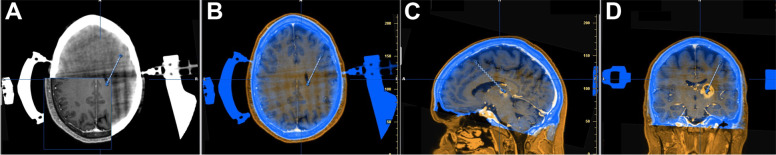

Fig. 2.

Computational merging of a planning MRI and the pre-procedural CT with the headrest in place in an exemplary patient. A Pre-procedural CT-scan with an inlet of the merged planning MRI. B axial, C sagittal and D coronal view of the planning T1-weighted contrast-enhanced MRI sequences (orange) with the merged native CT images (blue)

Intraoperative imaging for pre-procedural image merging (Fig. 2) as well as peri-procedural to verify the position of the biopsy cannula was successful in all patients. The mean radial trajectory deviation was 0.97 ± 0.39 mm at a biopsy depth of 60 ± 12.3 mm (mean ± standard deviation, Table 2). The interobserver (LS and OB) variability of the radial trajectory deviation was assessed in 4 patients and was below 0.1 mm.